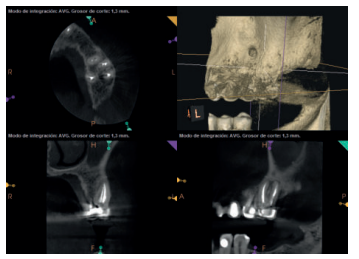

Para confirmar el origen endodóntico y el tamaño de las lesiones se realizaron exploraciones tomográficas con espesor de corte de 75 micras mediante CBCT CS8100 (Carestream Dental® ) en las que se evidenciaron lesiones periapicales radiolúcidas a nivel de 12, 11, 21 (con afectación bicortical), 25 y raíces vestibulares de 26 (Figuras 4 a 8).